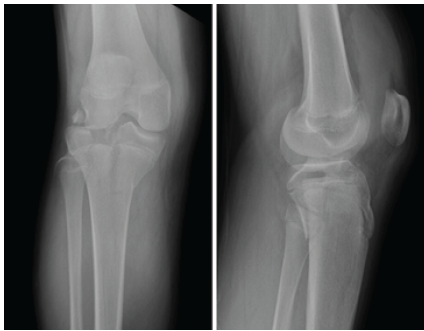

The patient is a 13-year-old male with no significant medical history who sustained a fall off a motorized scooter resulting in a right tibial plateau fracture and ipsilateral radial head fracture. On examination of his right lower extremity, his leg compartments were swollen but compressible. His motor and sensory function were grossly intact distally. Ankle-brachial index (ABI) was 0.92 and he had palpable pulses. X-rays demonstrated a Schatzker IV/Moore type 2 bicolumnar tibial plateau fracture-dislocation (Fig. 1).

Figure 1: Anteroposterior and lateral X-ray images demonstrating a Schatzker IV/Moore type 2 bicolumnar tibial plateau fracture-dislocation.